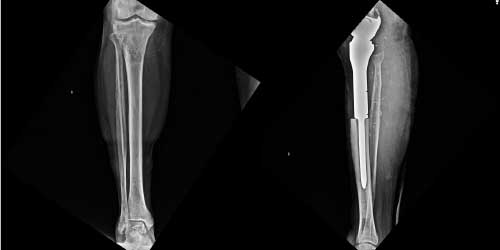

Omurga metastazı, kanserin ilk olarak iç organlarda gelişip daha sonra omurga kemiklerine yayılması sonucu oluşan bir durumdur. Çoğunlukla kan yoluyla sıçrayan bu tür metastaz, hastalarda sırt ve bel ağrısı gibi şikayetlerle kendini gösterir. Erken teşhis ve uygun tedavi yöntemleri, hastaların yaşam kalitesini artırmada kritik bir rol oynar.

Tedavide başarıyı artıran en önemli etkenlerden biri ameliyat öncesi iyi bir hazırlık ve cerrahi planlama yapmaktır. Her şeyden önce tanı doğru konmalı. Bunun için hasta iyi dinlenip, detaylı muayene edildikten sonra tetkikleri dikkatli incelenmelidir.

Her ameliyatın olduğu gibi kemik ve yumuşak doku tümör ameliyatlarının da riskleri vardır. Bu riskleri genel ve yapılan ameliyata özgü olmak üzere kabaca iki başlık halinde gruplandırabiliriz. Öncelikle anestezi ile ilgili risklerin anestezi uzmanı tarafından (...)